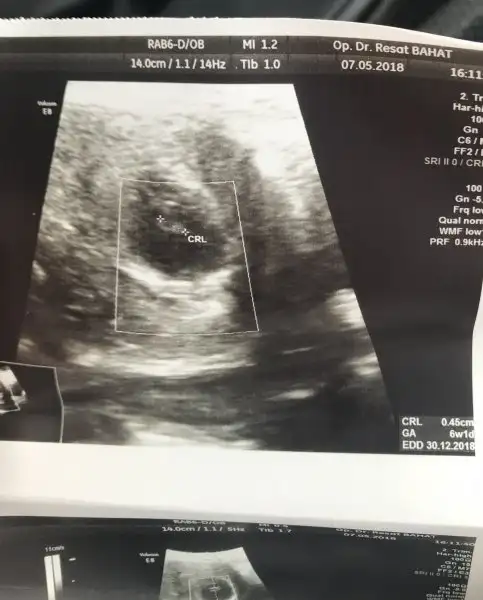

Cinsiyet nedir acaba 7+1 ama ultrasonda 6+4 çıktı

Eklentiler

• 220B77C1-8537-4B43-A9C6-45BE8AE7FBD9.webp

15,6 KB · Görüntüleme: 278